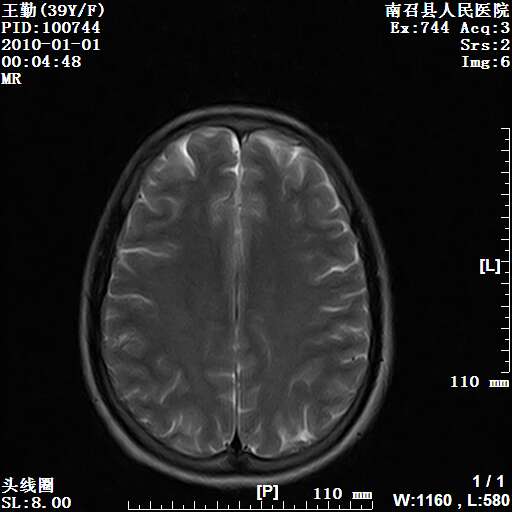

以下是引用随光逐影在2010-1-22 9:03:00的发言:[br]考虑左侧中颅窝(蝶骨翼区)脑膜瘤侵犯蝶骨翼并突入左侧眼眶。

以下是引用水过无痕在2010-1-22 14:55:00的发言:[br]一、定位:颅外占位;二、定性:恶性可能性大;三、组织来源:来源于左侧眼外直肌或其他部位;考虑为:横纹肌肉瘤>转移瘤>脑膜瘤.